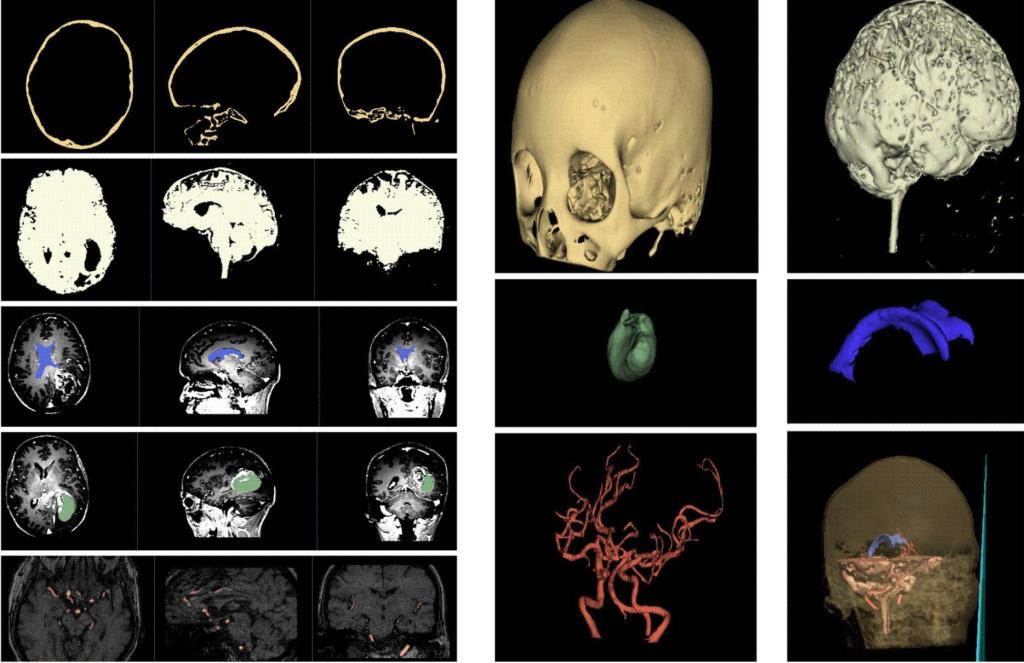

聚焦医疗虚拟现实及增强现实技术研究与应用,图形图像理论研究与应用,CT/MR医学图像数据重建三维模型,基于有限元的生物力学模拟并进行定性定量分析,为用户提供可交互且具有真实感的三维医学模型,力、震动传感与拟真研究与应用,主要研究虚拟现实、增强现实相关的交互技术,模拟力反馈,提高临场感与真实感。代表性研究成果如下:

医学三维重构及VR交互系统